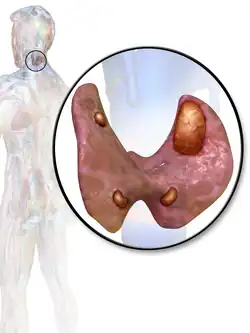

![]() | |

| 3D diagram of hyperparathyroidism | |

The parathyroid is composed of 4 glands with 2 located superiorly and 2 located inferiorly.[23] The parathyroid glands are located on the posterior thyroid and are derived from the endoderm of the 3rd and 4th pharyngeal pouches.[23] Specifically, the inferior parathyroid glands are derived from the 3rd pharyngeal pouch and the superior parathyroid glands are derived from the 4th pharyngeal pouch dorsal wing.[24] The ultimopharyngeal body is derived from the 4th pharyngeal pouch ventral wing and the parafollicular cells ( C-cells) are derived when the ultimopharyngeal bodies fuse with the posterolateral thyroid.[24] The parathyroid glands separates from the pharyngeal wall and attaches to the posterior thyroid during the 7th week of human embryonic development.[23]